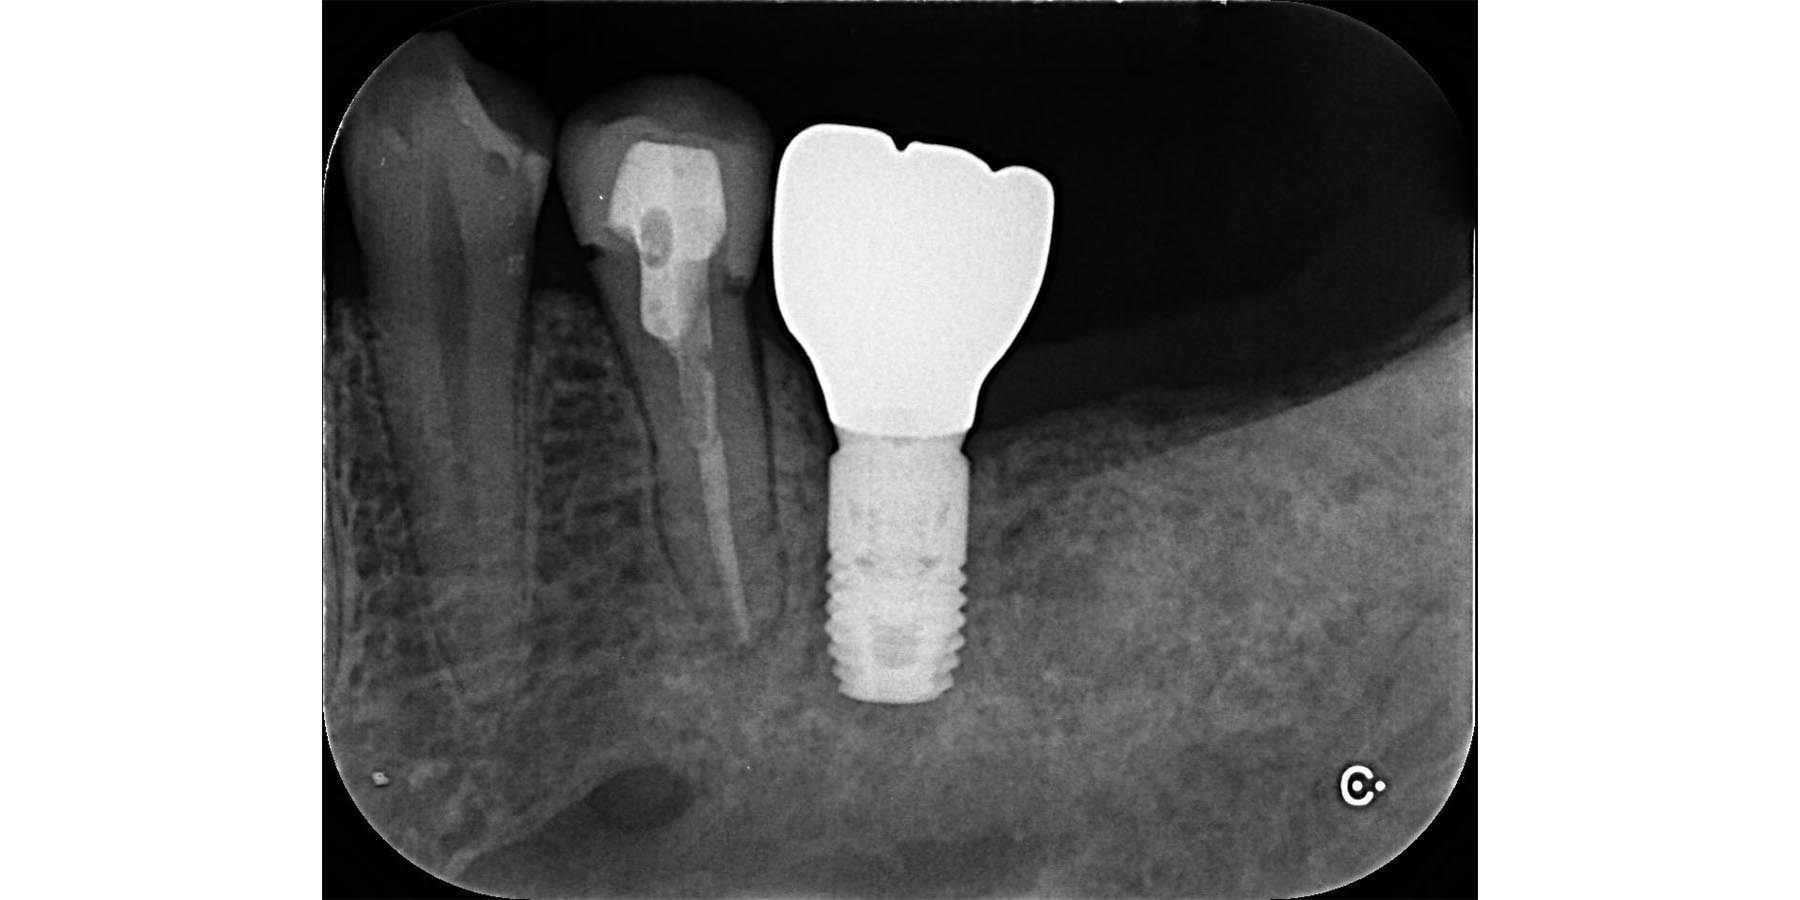

インプラント埋入後

被せ物セット完了

| 治療内容 | 左下5.7右下6のインプラント治療(3本) |